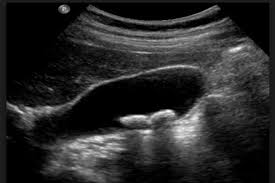

La Ecografía Abdominal, o Ultrasonografía Abdominal: Es el estudio de elección, el cual es rápido, indoloro y que tiene una sensibilidad del 95%, pudiendo estudiarse además, evaluar, las evaluar las características de la vesícula biliar y de los conductos biliares.

También se pueden utilizar otros medios diagnósticos, como el TAC (Tomografía Axial

Computerizada), la Colangio-Resonancia –Magnética (CRMN), pero la inicial, más económica, mas fácil de realizar, sin radiaciones, y sin molestas para el paciente es la

Ecografía abdominal, que además puede repetirse las veces que haga falta precisamente por esas características.